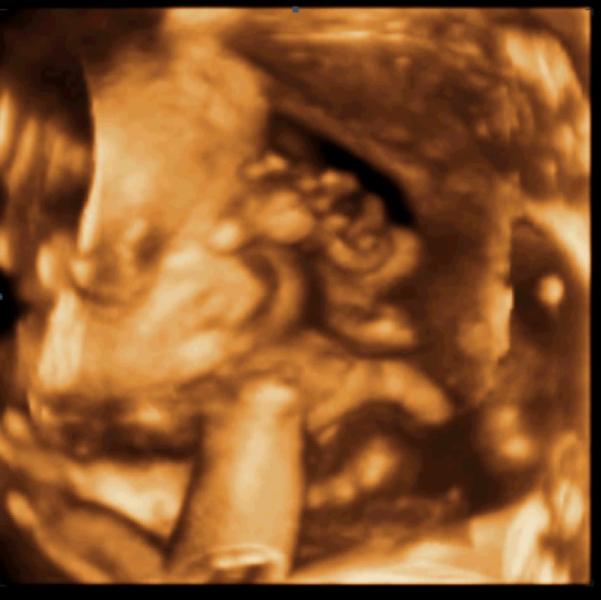

Сегодня сходили в Доктор Борменталь посмотреть на сына в формате 3D. Это незабываемо.

По совету @safru укачала малыша прогулкой до клиники. И подействовало, сын в начале исследования сладко спал.

Но он совсем не хотел показывать личико, закрывал его руками. После моих длительных уговоров и игр в прятки он все-таки показался.

О, Боже! Это чудо!

За время узи я успела и поплакать от счастья и испугаться до смерти, увидев якобы обвитие (при более детальном просмотре это не подтвердилось)...